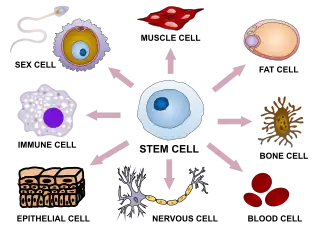

No specific therapy for LENAS is currently known or proven to cure this disease, but management of it should be immediately initiated following diagnosis. While more research should be taken, some suggest that hematopoietic stem cell transplantation may show a therapeutic role for this disease.[12]

Hematopoietic Stem Cell Therapy

Bone marrow is the soft spongy area in some larger bones of the body that produces many cells which make up red blood cells, white blood cells and platelets.[17] These cells are developed from a type of cell found in bone marrow, termed hematopoietic stem cells.[17] The body is able to direct these stem cells to develop in the blood at any given moment and this is a rapid process.[17] Most of the stem cells remain in the marrow until they are mature which then they are released for specific functions in the body such as carrying oxygen, providing infection protection, and helping blood clotting.[17] Stem cells found in circulating blood are able to be extracted for stem cell therapy use and research.[17]

A study done using hematopoietic stem cell therapy (HSCT) showed clinical benefit but suggested further exploration must be done.[18] Findings using HSCT was beneficial in recessive disorders and saw that it may similarly enhance CSF1R signaling after partial loss seen in LENAS.[18] In the subjects who had LENAS were introduced to HSCT and the finding of further progressed cells was minimal 15 years after the therapy was finished.[18] The most important finding in the subject was that they retained a high level of communication and survived beyond 15 years after onset of symptoms.[18] This is very rare for LENAS as it has been reported to be averaged at 6.8 years for surviving after the onset. This finding provides hope for future research direction and suggests that there may be great benefit to slow the progression of LENAS using HSCT.